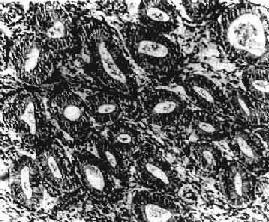

肉眼观,一般可见子宫内膜普遍增厚,可达0.5~1cm,表面光滑,柔软,也可呈不规则形或息肉状。镜下,可分4种类型:①单纯型,子宫内膜腺体及间质均增生,腺体明显增多、大小不一、分布不均(图13-6)。偶见腺体扩大成囊,腺上皮细胞呈柱状,缺乏分泌,往往排列成假复层。核分裂像常见。间质细胞排列紧密。②囊腺型,以增生腺体呈明显囊性扩张为特征。典型病例肉眼可见在增厚的内膜中有散在小孔形成,因此称之为瑞士干酪样增生。镜下,内膜腺体形状多样,大小极不一致,小者如增生早期的腺体,大者直径可为小的数倍至数十倍,大小腺体皆衬以假复层高柱状或立方上皮,并缺乏分泌现象。间质细胞丰富,胞浆少,核浓染。③腺瘤样型,以腺体增生而密集排列和间质稀少为特征,腺体数量远比前两型为多,结构也更加复杂,腺上皮向腺腔内呈乳头状或向间质呈出芽样增生。间质稀少。腺上皮细胞为高柱状,假复层,核空泡状,核分裂像常见,但无明显异型性。④不典型增生,组织结构与腺瘤样增生相似,腺体拥挤并呈不规则形、分支状或出芽样增生,间质明显减少,同时出现腺上皮细胞的异型性,细胞核大,染色质粗,核仁明显,上皮复层,失去极性,常见核分裂像。子宫内膜不典型增生有时很难与高分化腺癌鉴别,主要鉴别点是前者不见间质浸润。有人认为它是子宫内膜腺癌的癌前变化。

图13-6 子宫内膜增生症

腺体明显增多、大小不一、分布不均,腺上皮多层,间质增生,排列紧密